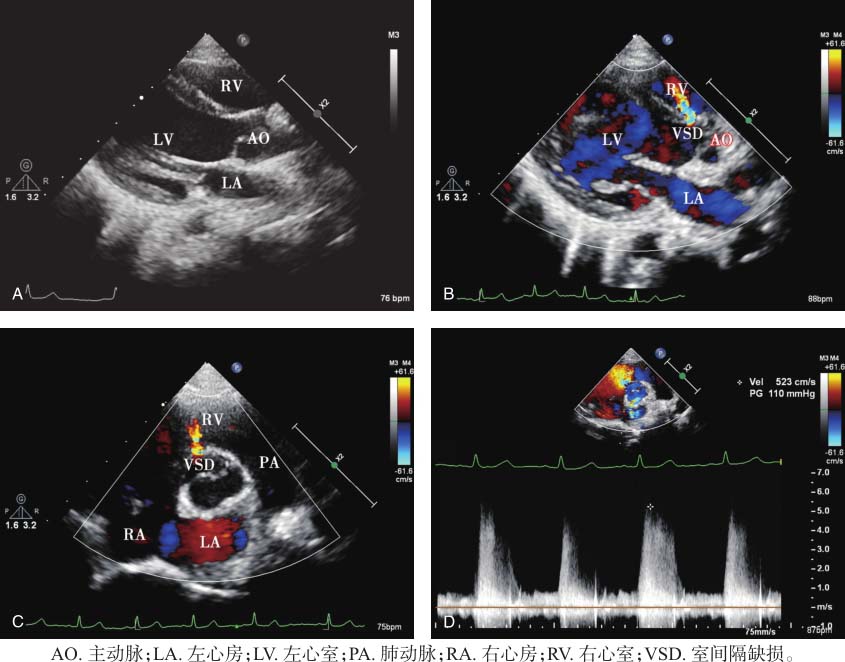

收缩期心室水平探及左向右高速分流信号,峰值流速523cm/s,峰值压差110mmHg。见图6-1。

图6-1 患儿超声心动图表现

A.胸骨旁左心室长轴切面显示左心房、左心室及右心室内径大致正常;B.胸骨旁左心室长轴切面彩色多普勒显示左向右分流信号;C.胸骨旁大动脉短轴切面彩色多普勒显示左向右分流信号;D.连续多普勒测量左向右分流峰值流速523cm/s,峰值压差110mmHg。

二维超声显示室间隔回声明确中断,胸骨旁大动脉短轴切面显示缺损位于约12点方向,近室上嵴处,为嵴内型。缺损较小,左心房、左心室前负荷增加不明显,因此内径大致正常。彩色多普勒显示左右心室之间为左向右高速分流,连续多普勒测量分流峰值流速523cm/s,峰值压差110mmHg,据此计算肺动脉收缩压不高,患儿尚未出现肺动脉高压。最终诊断为室间隔缺损(嵴内型)。